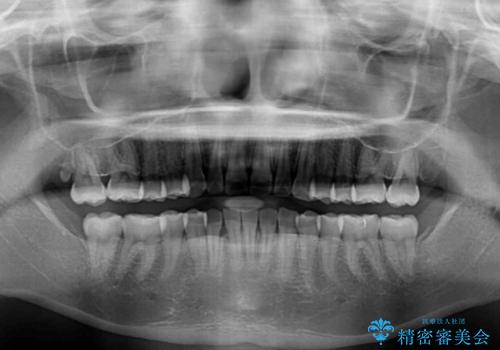

患者様も驚く、僅か10か月での治療終了となりました。

下顎前歯が1歯欠損しているため、上下正中は合わず、左右奥歯の咬み合わせは理想的とはならない仕上がりとなります。